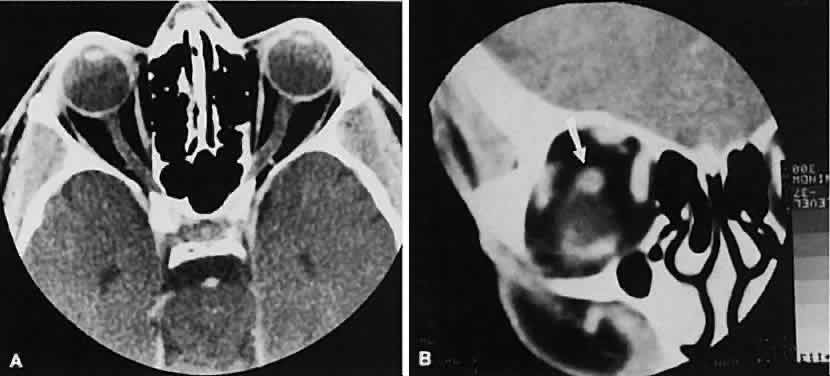

Dermoid cysts are located most frequently in the superior temporal quadrant of the orbit. They may be located anywhere within the orbital confines. Lesions in the lacrimal fossa or along the posterior lateral wall may communicate intracranially or into the temporalis fossa. Radiographically, the cysts are well-delineated and have lucent interiors with CT attenuation densities in the fat range (Fig. 19). Calcification along the rim of the cyst may be present. The bony changes have irregular, notched borders rather than the moth-eaten appearance associated with malignancy. The range of CT appearances can be quite wide.67

Fig. 19. Axial (A) and coronal (B) scans of a dermoid cyst. Note the low attenuation (lower than retrobulbar fat) within the well-demarcated cyst located in the right lacrimal gland fossa.